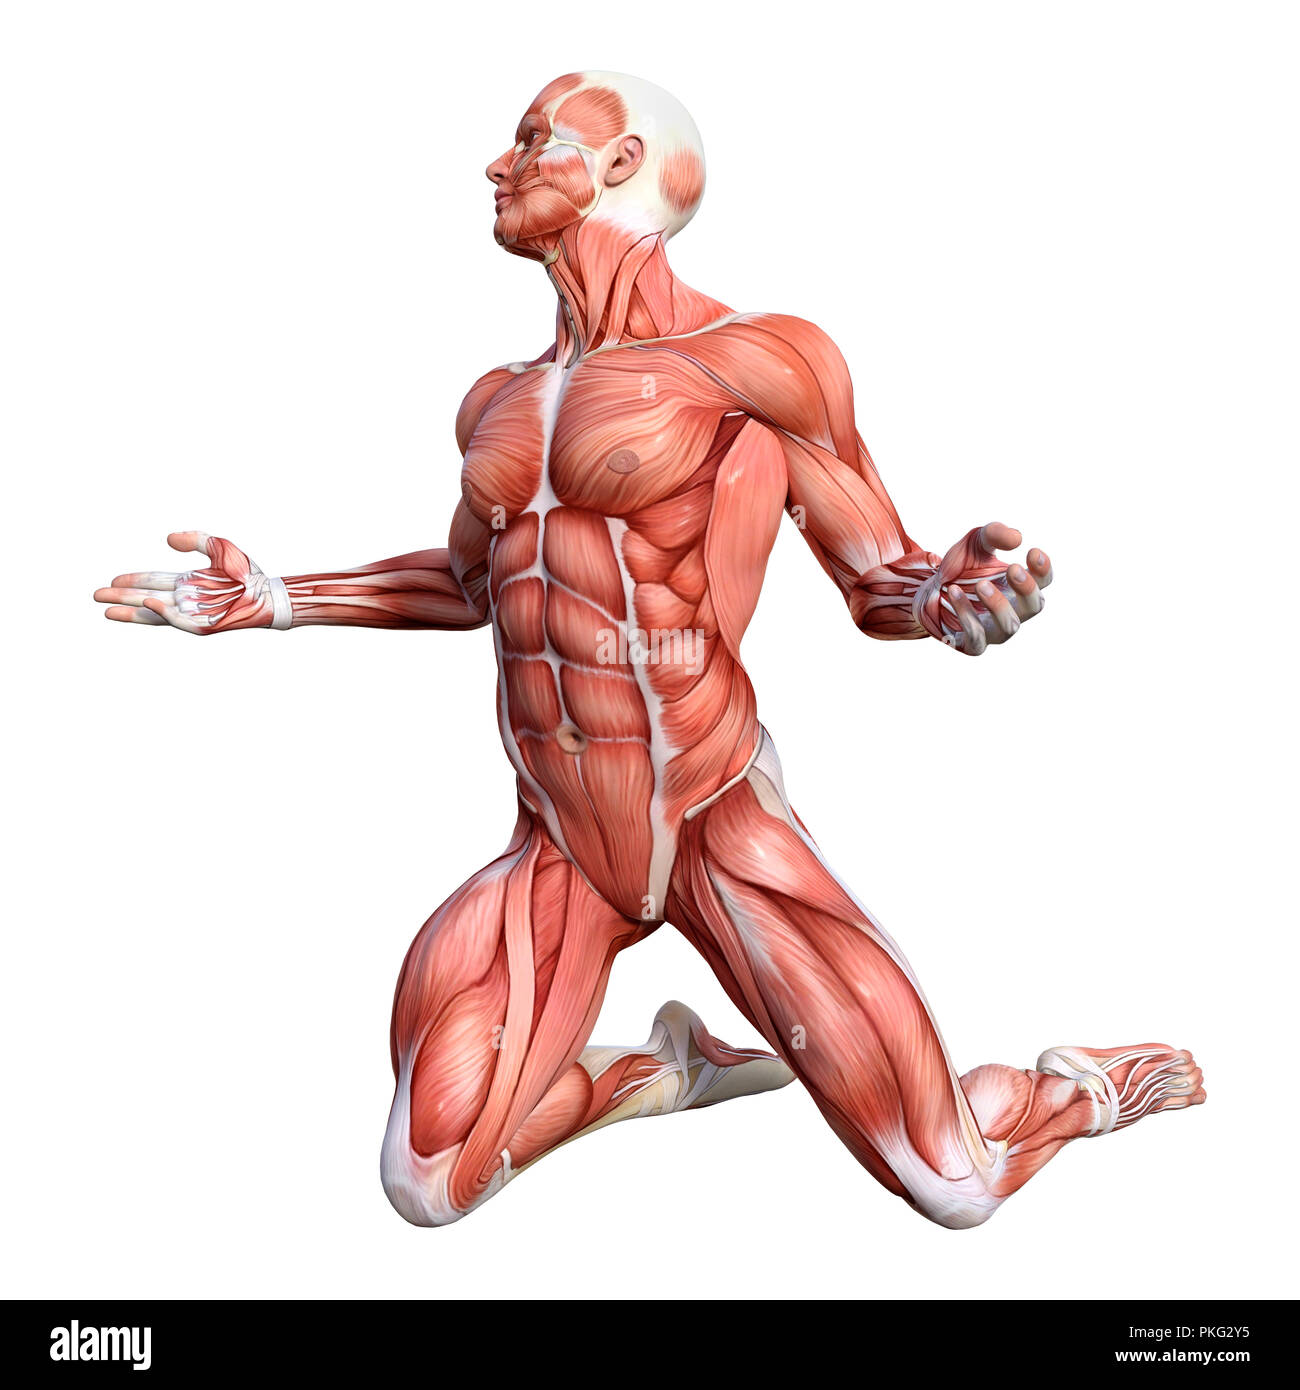

RFPKG2Y5–3D-Rendering einer männlichen Anatomie-Figur mit Muskeln Karte isolierten auf weißen Hintergrund